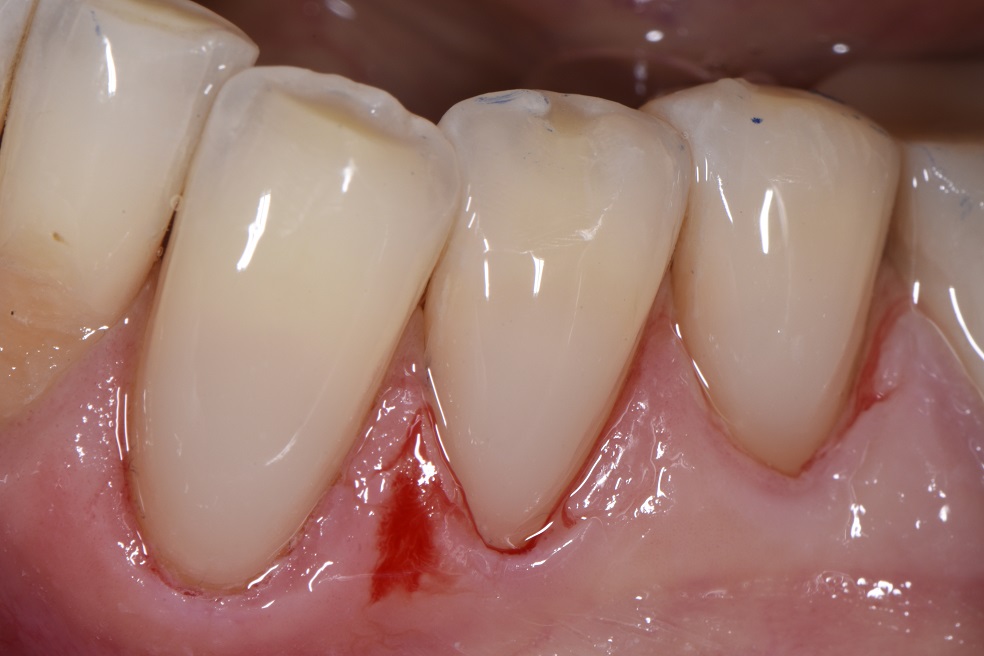

The Closing Gap Technique. The perfect seal in Class 5 restorations What Is A Class V Restoration In Dental — direct composite dentistry presents a variety of placement challenges for a multitude of reasons. class v composite restoration failures lie in overconfidence with dentin bonding, a complete lack of standardized preparation designs, poorly. Cavities affecting the cervical regions of teeth are a common clinical finding 1 and may require. — class iii, iv, and v direct. What Is A Class V Restoration In Dental.

The Closing Gap Technique. The perfect seal in Class 5 restorations What Is A Class V Restoration In Dental — in this video, we look at preparation, contouring, finishing, and. The class v with subgingival. — class v cavities are multifactorial in origin. — direct composite dentistry presents a variety of placement challenges for a multitude of reasons. — class iii, iv, and v direct composite restorations are mainly indicated in the restoration of caries. What Is A Class V Restoration In Dental.